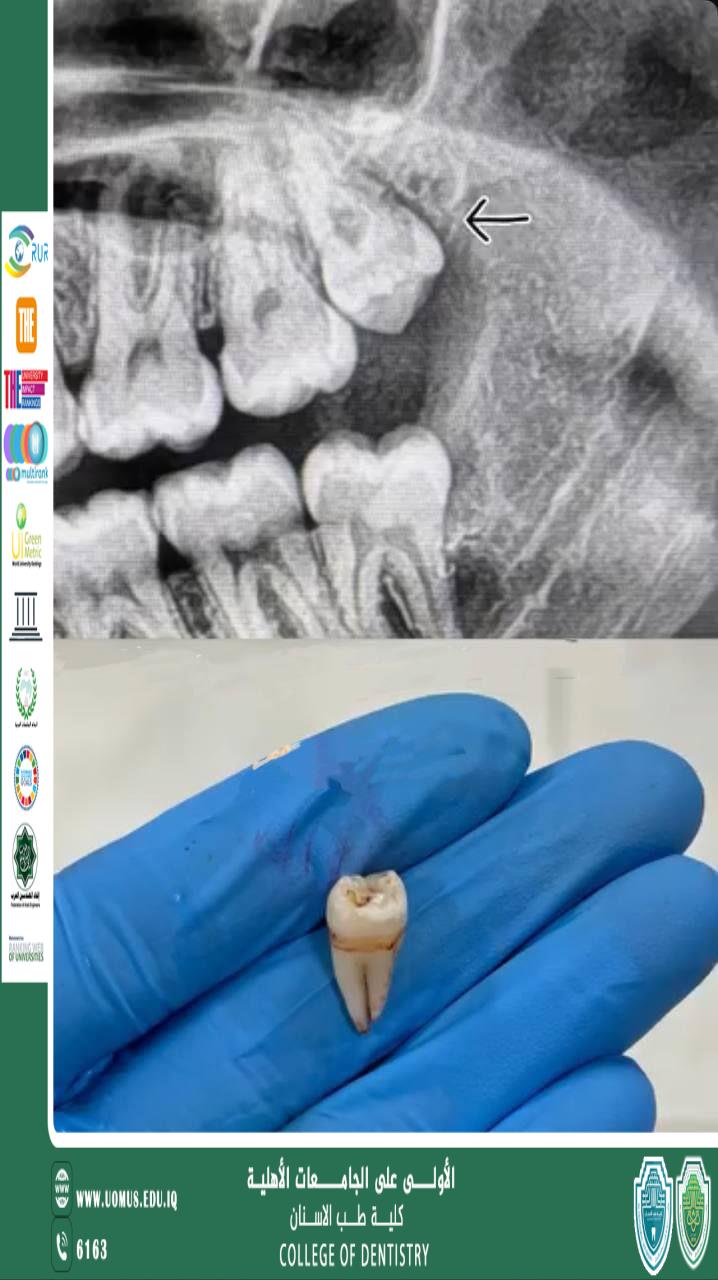

أبداع أحد طلبة كلية طب الأسنان المرحلة الخامسة في عملة داخل العيادات التعليمية

جانب من إبداع الطالب مرتضى محمد عبدالزهراء أحد طلبة كلية طب الأسنان المرحلة الخامسة الذي أبدع في الجانب العملي من خلال عمله داخل العيادات التعليمية لكلية طب الاسنان وقد لاقى هذا الأداء استحسانًا من قبل أساتذتة الذين أثنوا على جهوده وأشادوا بتفانيه وتميز . <br />مع تمنياتنا لجميع طلبتنا بالتوفيق والنجاح في المراحل القادمة .<br /><br />جامعة المستقبل الجامعة الاولى في العراق .<br /><br />